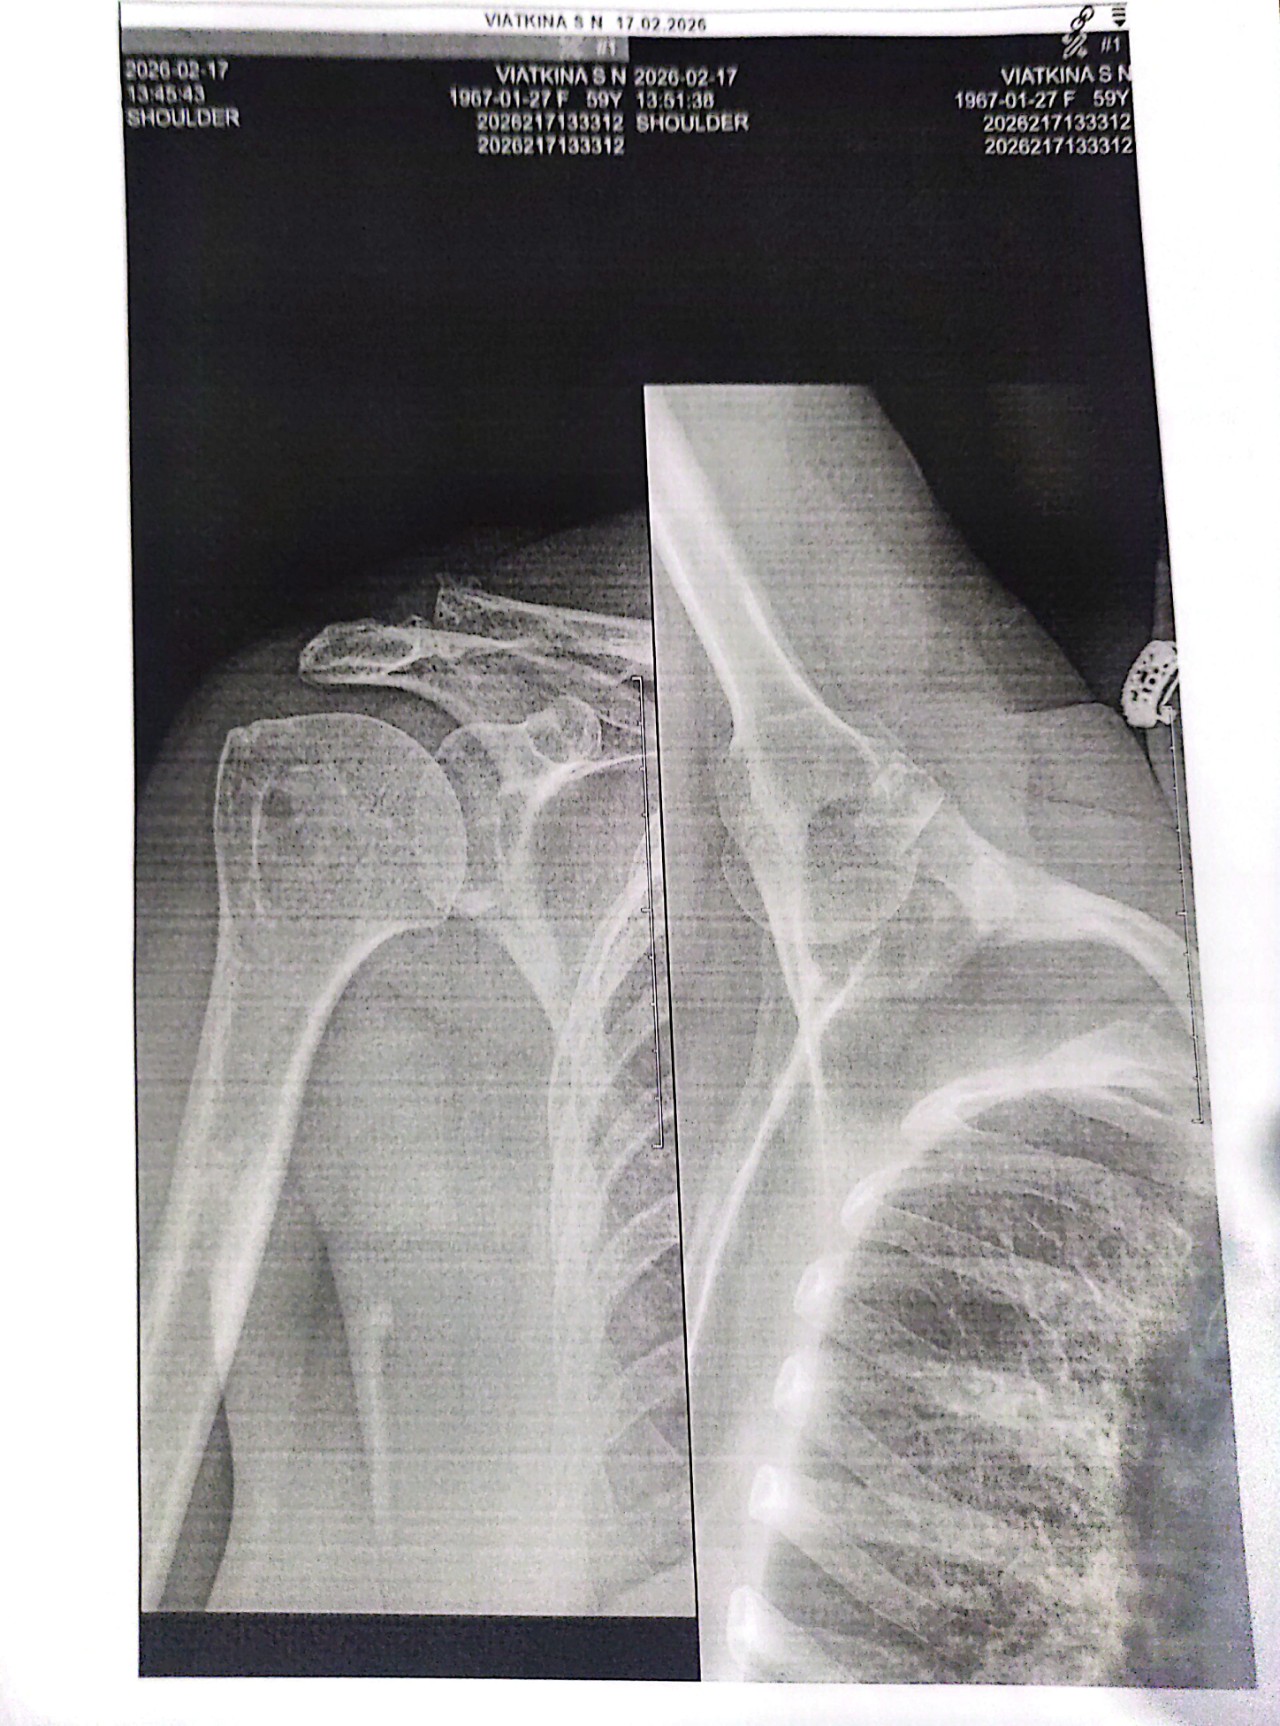

Здравствуйте, Упала на правую руку ударилась локтем, болит сильно, не могу поднять вверх и отвести назад. Отека, синяка, кровоподтёка нет. Сделала рентген плечевого сустава в 2 х проекциях можете расшифровать